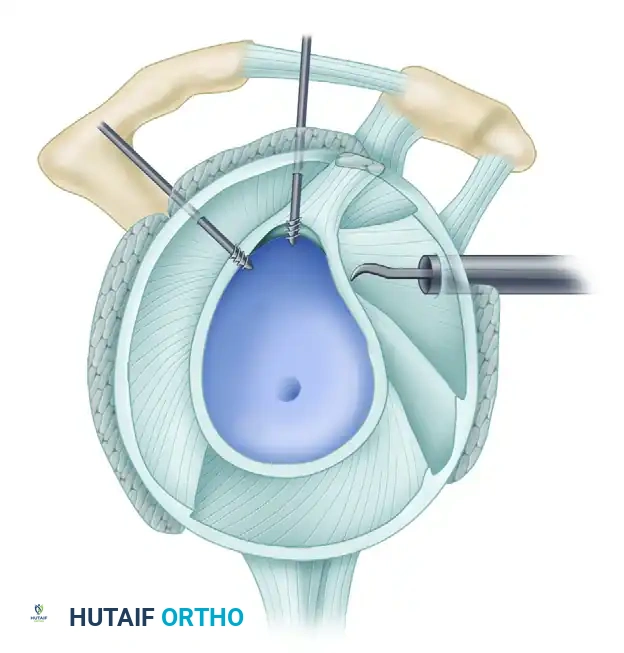

3. Anterior Anchor Placement

Transition to the anterior Bankart repair. The goal is to secure anatomical fixation 2 mm onto the articular surface with a minimum of three (preferably four) suture anchors, spaced 5 to 7 mm apart.

A, Capsule and labral complex freed.

The Inferior Anchor (The Keystone):

The most critical anchor is the most inferior one. Use the 5-o’clock percutaneous portal with a spinal needle for precise trajectory (45-degree angle to the articular surface). Place the spear guide at the 5:30 position, 1 to 2 mm onto the articular cartilage margin. Drill and insert a biocomposite or all-suture anchor (e.g., JuggerKnot).

B, Anchor inserted on articular edge.